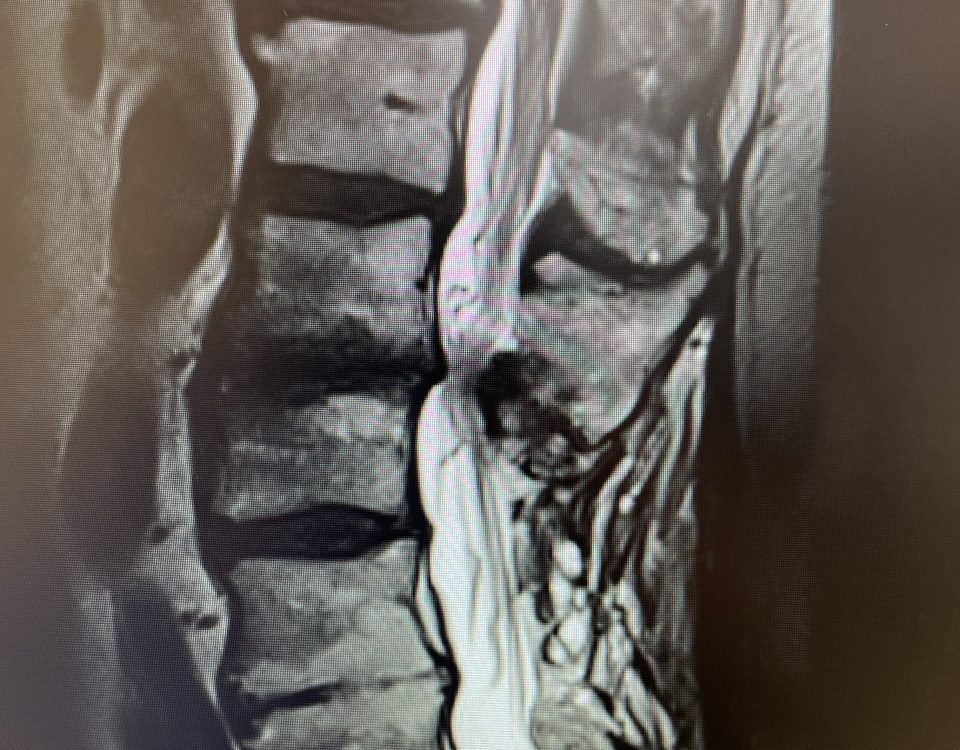

Here is a tough case: This is a 72 year-old male who presented with several months of progressive neck pain without symptoms of the arms or legs. […]